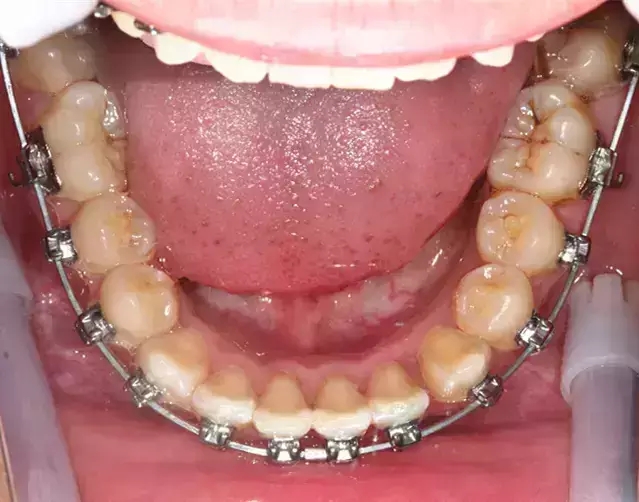

Damon 病例分享:安氏 II 類(lèi)二分類(lèi)露齦笑的矯治(董一磊)

治療前后對(duì)比